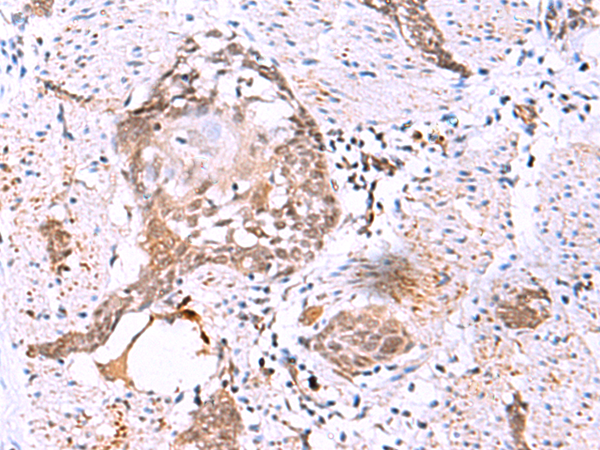

IHC positive control: |

Human esophagus cancer |